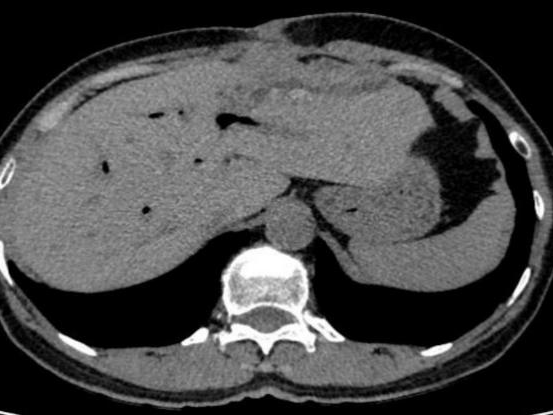

结果检查一看:患者肝内胆管存在多发结石并伴有胆管扩张。由于结石长期在体内“作祟”,引发了局部组织的严重炎症和破溃,最终导致肝脏穿孔,并与腹壁形成了一条异常的“窦道”(瘘管)。这条通道使得肝脏内的感染物直接穿出腹壁,造成了腹壁流脓的危重局面。

张继红教授带领手术团队沉着应对、精准操作,小心翼翼地层层分离粘连组织,逐步梳理紊乱的解剖结构,最终发现肝左叶与腹壁之间形成了约1cm宽的致密瘘管,管内可见少量白色分泌物,正是这处“漏点”导致患者腹壁反复流脓。在精准保护周围肠管、重要血管不受损伤的前提下,团队成功切除病变的左半肝,彻底清除病灶。

术后解剖离体肝脏标本发现,患者肝内胆管扩张明显,内有多发褐色结石,最大直径达1×1cm,这些结石长期反复刺激胆管壁,正是引发肝脏穿孔、腹壁流脓的根本原因。